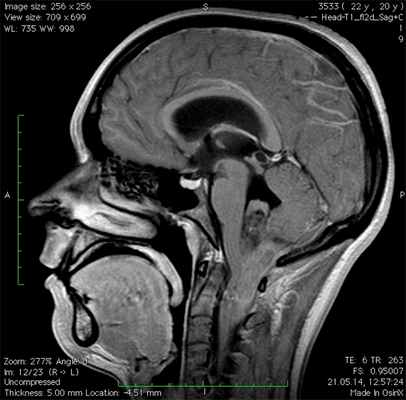

МРТ и КТ

Первичным методом визуализации, используемым для диагностики эпендимомы, как правило, является МРТ, дающая возможность получить многоплоскостное и высококонтрастное изображение мягких тканей. Однако в некоторых случаях у детей сперва проводят КТ, которая дает более точную информацию о наличии кальцификатов в опухоли.

В любом случае, именно по результатам МРТ и КТ определяют точную локализацию, размеры и структуру опухоли, возможные сосудистые сплетения и другие параметры, необходимые для принятия решения о степени хирургического вмешательства и применения других методов лечения.

Диагностическая визуализация

Обнаружить опухоль помогают методы диагностической визуализации. Основным методом визуализации, который обычно используется для оценки эпендимомы, является магнитно-резонансная томография (МРТ) головного и спинного мозга. Кроме того, МРТ проводится после хирургической операции, чтобы удостовериться, что опухоль удалена полностью.